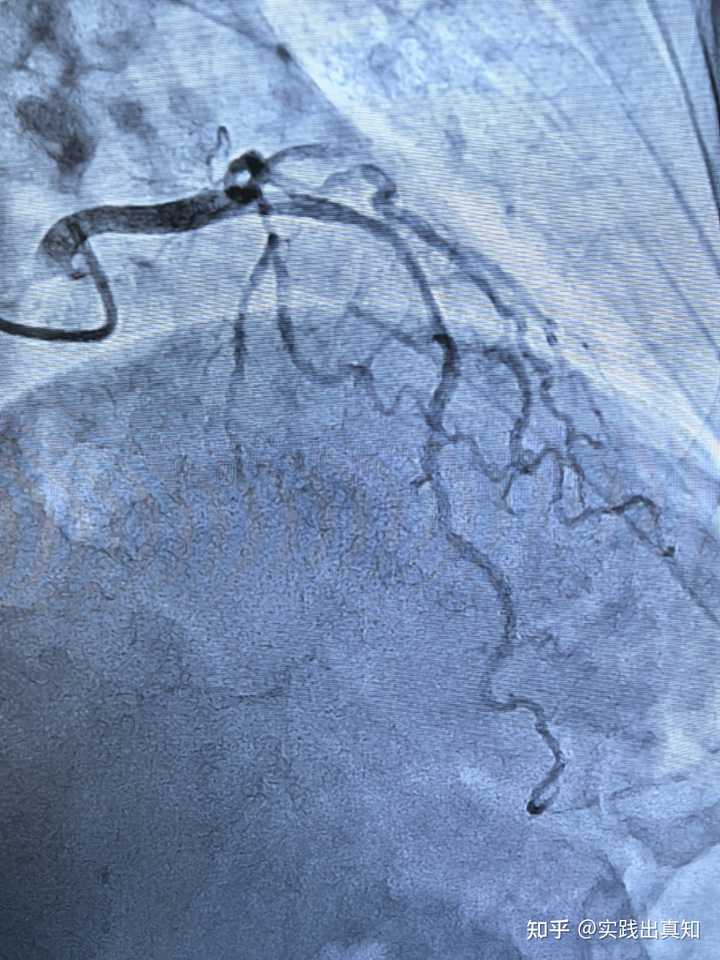

心脏彩超无法清晰地显示冠状动脉的内部情况。冠状动脉的直径只有几毫米,而彩超的分辨率有限,无法判断里面是否有动脉粥样硬化斑块、狭窄或者血栓。诊断冠状动脉需要做冠状动脉CTA(冠脉造影)。

要知道冠脉ct或者冠脉造影不是常规体检!造影剂对肾脏有不小代谢负担,而且很多人对造影剂过敏

这是因为冠心病本质上属于冠状动脉血管的血管壁疾病。对于血管壁,常规的体检无能为力。虽然目前有一些比较专业的检查手段,如造影时做FFR(血流储备分数)、IVUS(血管内超声),这些检查能够发现斑块,但即便发现斑块,也不能预测什么时候会发生斑块破裂,形成血栓。